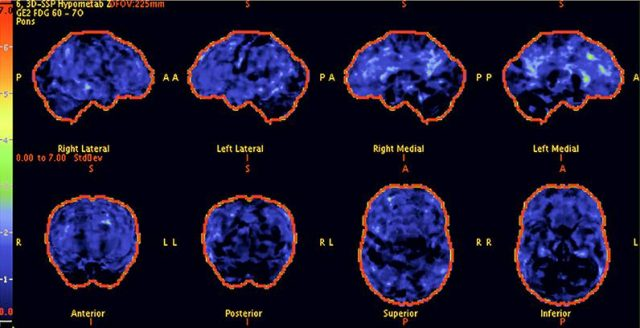

Above: The patient’s PET scan after AlzClipp treatment shows improvement, with cognitive abilities greatly enhanced as the scan approaches that of a normal brain.

Above: A 68-year-old woman with a 10-year history of cognitive issues. Previous PET scans showed significant metabolic decline, indicating Alzheimer’s.